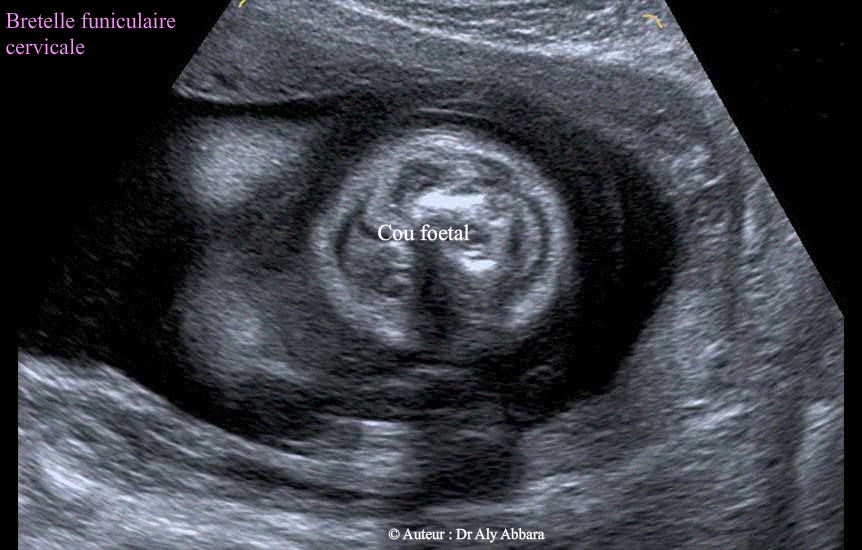

Bretelle funiculaire cervicale,- Images 2D

• Bretelle cervicale du cordon ombilical :

• Images échographiques en 2D, puis en 3D mettant en évidence la présence d'une bretelle funiculaire autour du cou fœtal :

• 1- Une bretelle-cravate à anse postérieur (images 2D et première image 3D)